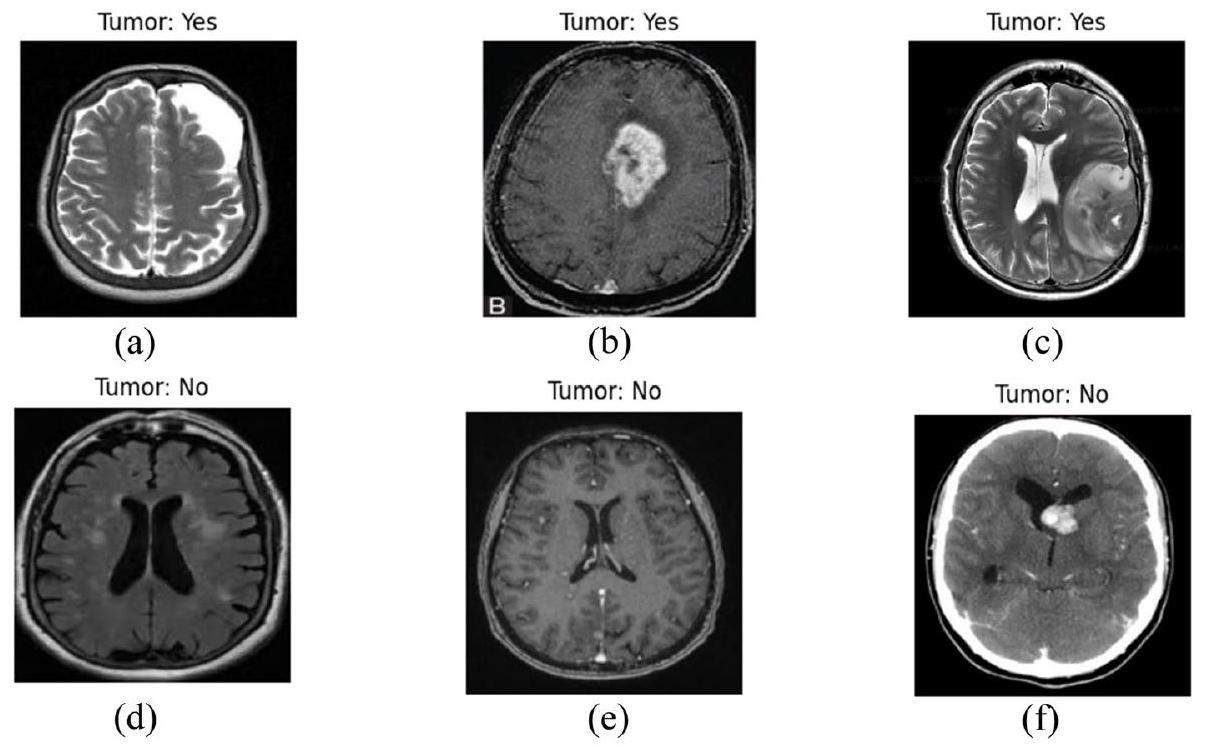

تعزيز اكتشاف أورام الدماغ في صور الرنين المغناطيسي من خلال الذكاء الاصطناعي القابل للتفسير باستخدام Grad-CAM مع Resnet 50 Enhancing brain tumor detection in MRI images through explainable AI using Grad-CAM with Resnet 50

تتناول هذه الدراسة التحدي الحاسم في الكشف عن أورام الدماغ باستخدام صور الرنين المغناطيسي، وهي مهمة محورية في التشخيص الطبي تتطلب دقة عالية وقابلية للتفسير. بينما أظهر التعلم العميق نجاحًا ملحوظًا في تحليل الصور الطبية، لا يزال هناك حاجة كبيرة لنماذج ليست دقيقة فحسب، بل قابلة للتفسير أيضًا لمهنيي الرعاية الصحية. غالبًا ما تعمل المنهجيات…